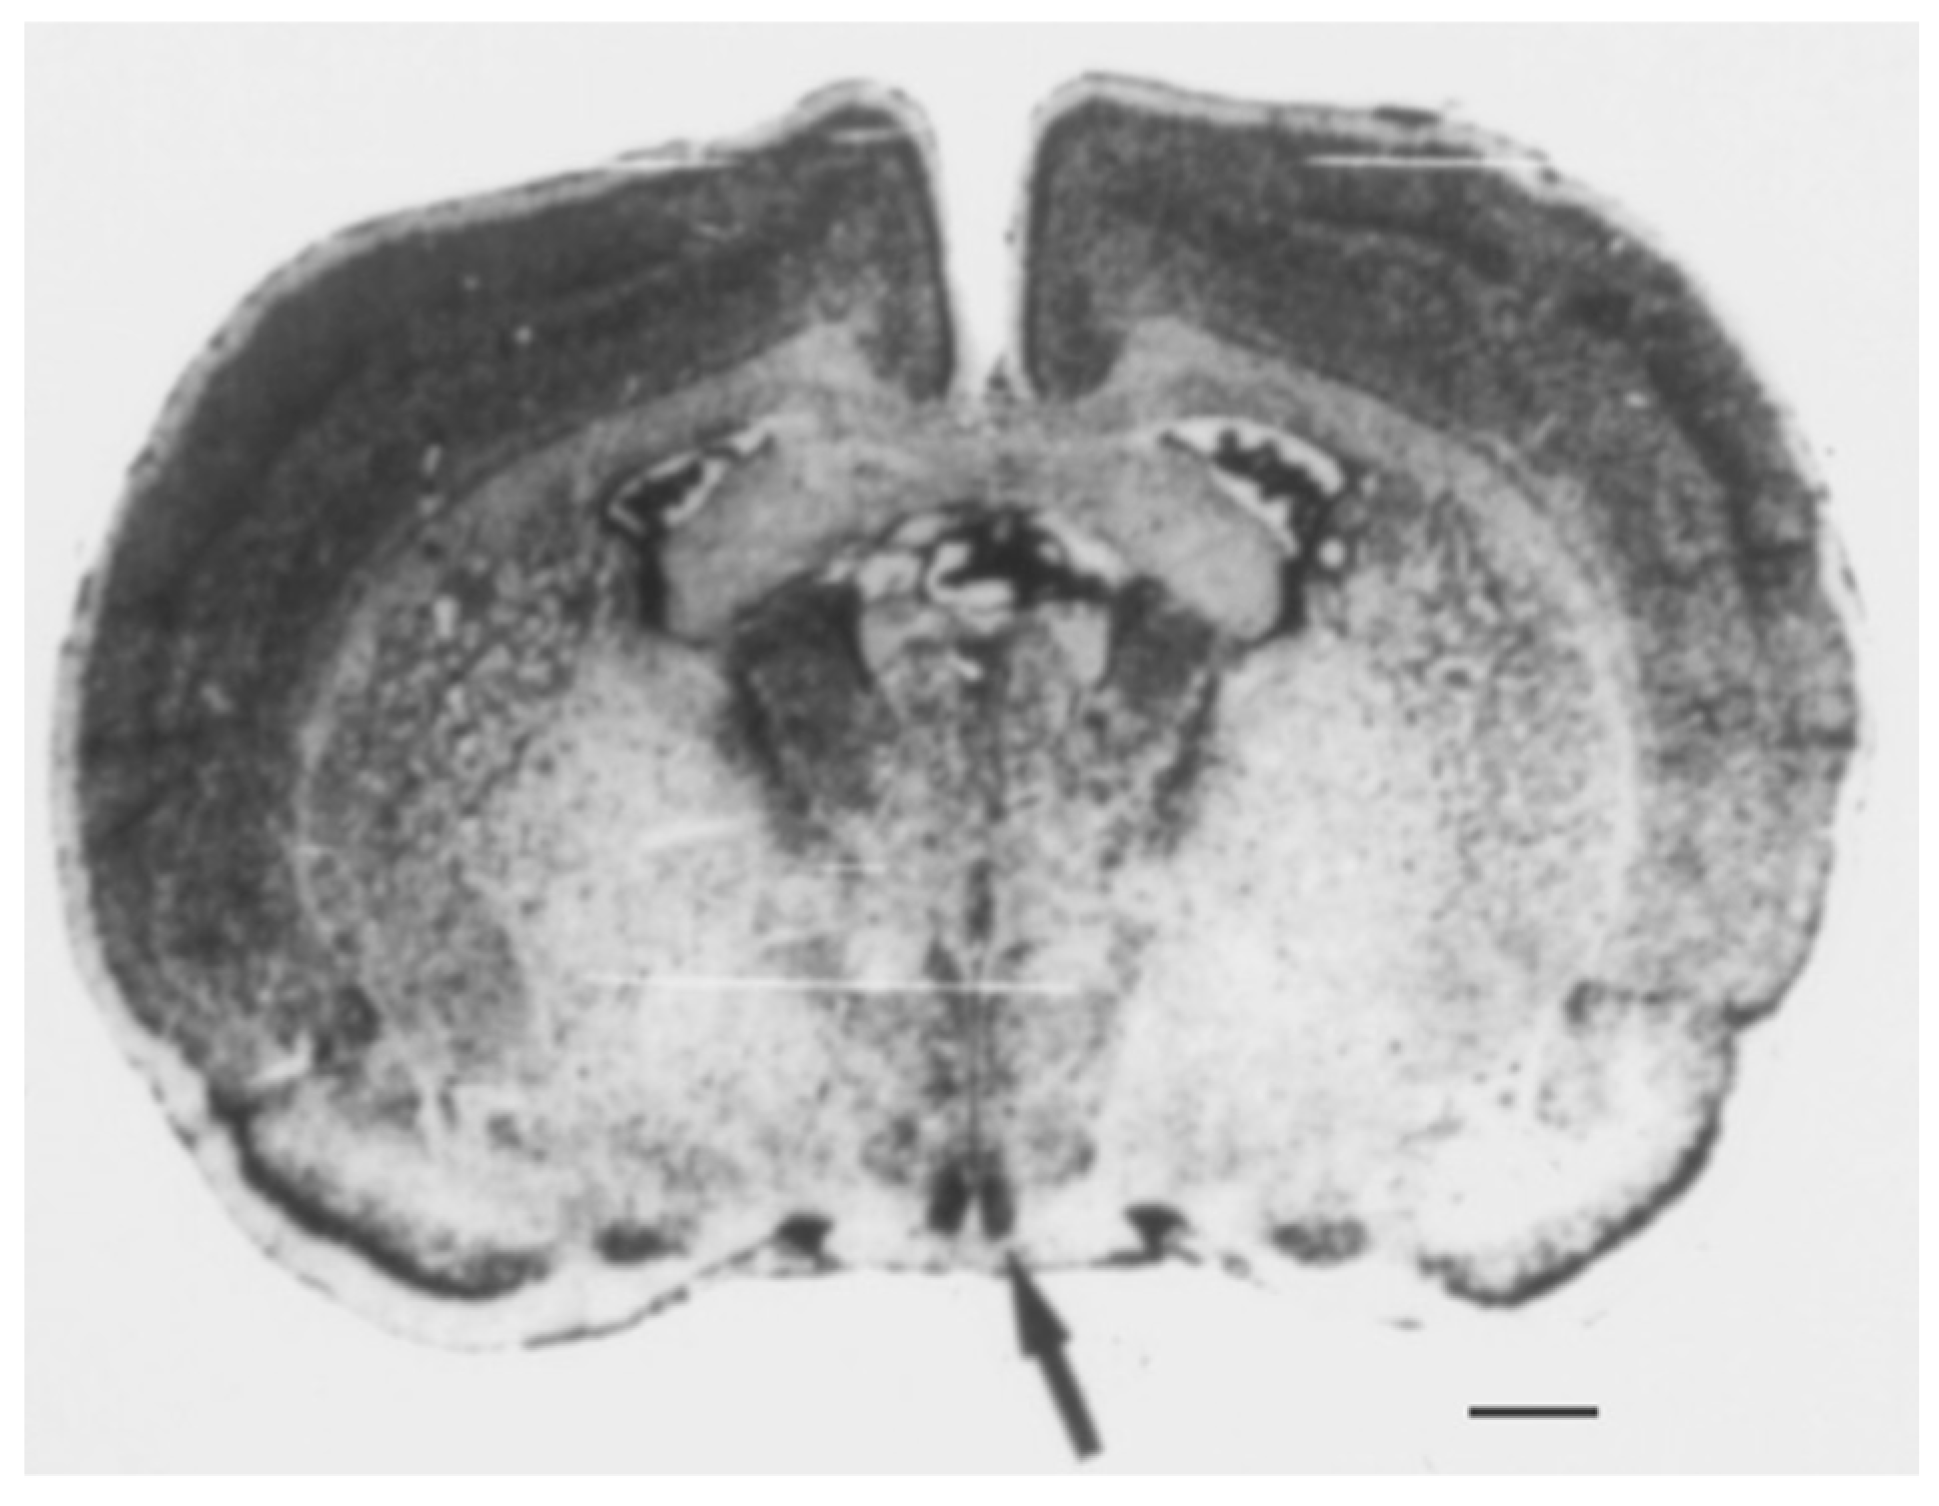

2. The SCN of the Hypothalamus

- Abrahamson, E.E.; Moore, R.Y. Suprachiasmatic nucleus in the mouse: Retinal innervation, intrinsic organization and efferent projections. Brain Res. 2001, 916, 172–191. [Google Scholar] [CrossRef] [PubMed]

- Lokshin, M.; LeSauter, J.; Silver, R. Selective distribution of retinal input to mouse SCN revealed in analysis of sagittal sections. J. Biol. Rhythms 2015, 30, 251–257. [Google Scholar] [CrossRef] [PubMed]